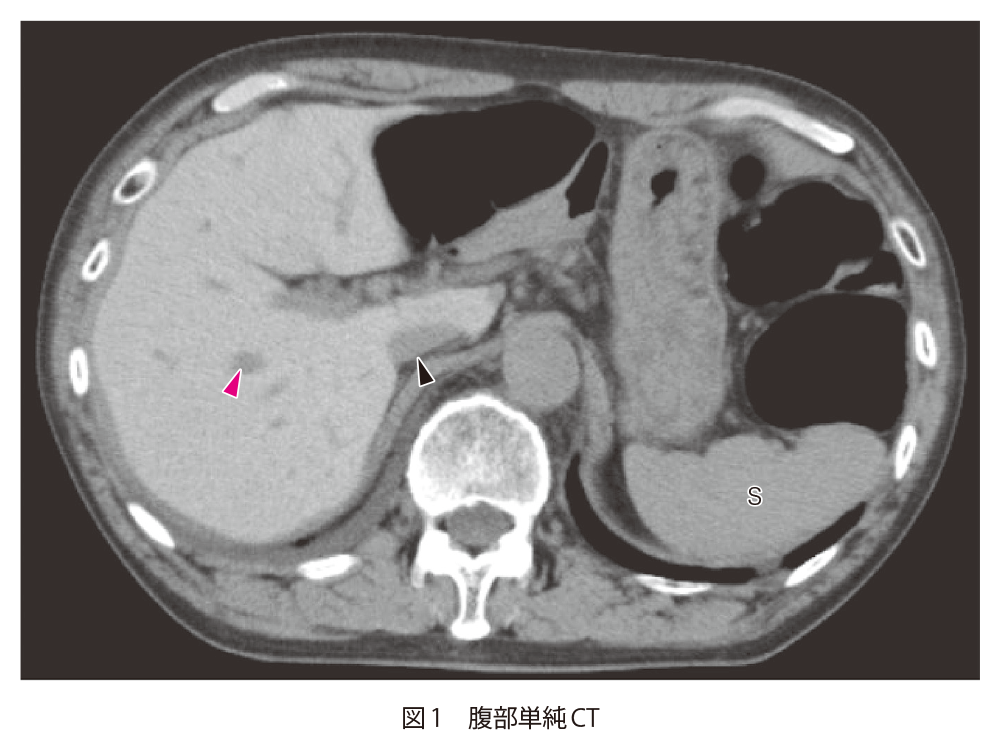

閉塞性肥大型心筋症で通院中の70歳代男性 70歳代男性.閉塞性肥大型心筋症で定期受診中.数年前に植込み型除細動器(implantable cardioverter defibrillator:ICD)を植込み済.数日前より便秘,腹部膨満感,腹痛があり来院.腸閉塞が疑われ,精査のために単純CTが撮影された. A1.肝実質がびまん性に高吸収になっているA2.アミオダロンや鉄剤の内服歴,頻回の輸血歴などがないかを確認するA3.アミオダロン肝 1.読影のポイント 単純CTで肝実質がびまん性に高吸収に描出されている.肝実質と門脈(図1▶︎),IVC(inferior vena cava:下大静脈,図1▶︎)とのコントラストが増強しており,脾臓(図1 S)と比較しても肝実質が高吸収になっていることがわかる.びまん性に濃度変化を生じていると,一目では変化に気がつかないことがある.比較画像がある場合はその画像との対比を,比較画像がない場合には周囲にある構造と濃度を比較することで,変化や異常に気がつきやすくなる.今回の場合では,肝実質と肝内血管の濃度差,肝実質と脾臓の濃度差に気がつけるかどうかが最大のポイントとなる. この症例では,ICDの植込み歴があり,アミオダロン肝と診断された.塩酸アミオダロンは抗不整脈薬の1つで,脂溶性のため,脂肪組織や肺,膵臓,肝臓,心臓,腎臓に蓄積されることが知られている.ヨードを含有しているため,肝臓に蓄積すると肝実質が高吸収を示す. 2.鑑別診断 単純CTで肝臓がびまん性に高吸収になる場合,原子番号が高い元素(鉄,金,銅,ヨードなどの金属)や高分子化合物が沈着していることが考えられる.鉄が蓄積するヘモクロマトーシス/ヘモジデローシス,銅が沈着するWilson病などが疾患としては有名である.これらは画像のみでの鑑別は難しく,臨床情報が非常に重要となる. 3.次の一手 診断には臨床情報が非常に重要である.特に内服薬や既往歴,頻回の輸血がないかどうかの確認が重要となってくる.既往に不整脈やペースメーカー/ICDの植込みがある場合にはアミオダロン内服によるアミオダロン肝の可能性を,鉄剤の内服や静注などがある場合にはヘモクロマトーシス/ヘモジデローシスを考慮する必要がある. 図2にヘモジデローシスの症例を示す.アミオダロン肝と同様に,肝臓がびまん性に高吸収になっており,肝内血管(図2*)とのコントラストが増強している.この症例では,頻回の輸血歴があり,血清フェリチン値も高値(>1,000μg/dL)を示しており,輸血後鉄過剰症と診断されている.ヘモクロマトーシス/ヘモジデローシスの診断にはMRIが有用で,鉄の沈着を反映して,T2強調像やT2*強調像で信号低下がみられる. 救急医Check Point アミオダロンは心室細動,心室頻拍や心不全(低心機能)または閉塞性肥大型心筋症に伴う心房細動などの再発性不整脈において他の抗不整脈薬が無効,または使用できない場合に使用される薬剤である.非常に有効な薬剤である反面,肺(間質性肺炎,肺線維症,肺胞炎),心臓(既存の不整脈の重度の悪化,Torsades de pointes,心不全,徐脈,完全房室ブロックなど),肝臓(劇症肝炎)などの致死的となりうる副作用が報告されている. アミオダロン肝は除外診断であるためで1),血液生化学検査によるトランスアミナーゼや肝炎ウイルスの検査などその他の原因による肝疾患の精査を消化器内科など専門医に依頼する必要がある.肺野病変を認める場合も呼吸器内科など専門医に紹介する.また,副作用の発現が疑われた場合,重篤化すると致死的となる可能性もあるため,処方医にアミオダロンの必要性について再検討を依頼し,肝臓,肺などの専門医と連携して薬剤量を調整してもらうように依頼する. 文献:1)Hussain N, et al:Amiodarone-induced cirrhosis of liver:what predicts mortality? ISRN Cardiol,2013:617943, 2013 文献・参考文献 「肝胆膵の画像診断-CT・MRIを中心に-」(山下康行/編著),学研メディカル秀潤社,2010 「腹部のCT第3版」(陣崎雅弘/編),メディカル・サイエンス・インターナショナル,2017 「肝胆膵のCT・MRI」(本田 浩,他/編),メディカル・サイエンス・インターナショナル,2016 「肝の画像診断 画像の成り立ちと病理・病態 (第2版)」(松井 修,他/編著),医学書院,2019 (2020/5/12公開) 戻る この"ドリル"の掲載書をご紹介します レジデントノート増刊 Vol.22 No.2画像診断ドリル救急医と放射線科医が伝授する適切なオーダーと読影法 藪田 実,篠塚 健/編 定価:4,700円+税 在庫:あり 月刊レジデントノート 最新号 次号案内 バックナンバー 連載一覧 定期購読案内 定期購読WEB版サービス 定期購読申込状況 レジデントノート増刊 最新号 次号案内 バックナンバー 定期購読案内 residentnote @Yodosha_RN その他の羊土社のページ ウェブGノート 実験医学online 教科書・サブテキスト 広告出稿をお考えの方へ 広告出稿の案内